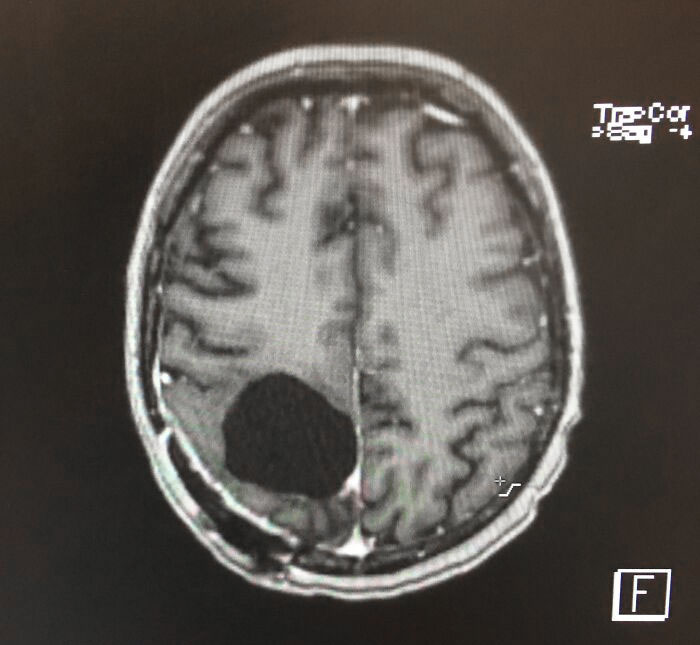

I Had A Brain Tumor Removed, And Now I’m A Bit Absent Minded